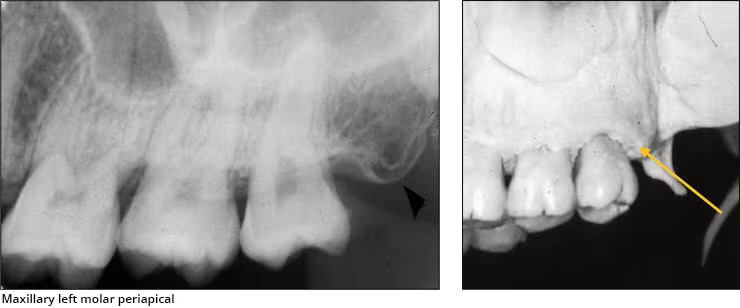

Coronoid process

Anterosuperior portion of the ramus

Seen when the patient’s mouth is open on posterior maxillary PA’s

Hamular process

aka pterygoid hamulus

Tiny finger/hook like projection of bone extending from medial pterygoid plate.

Appears on maxillary molar PA’s and molar bitewings